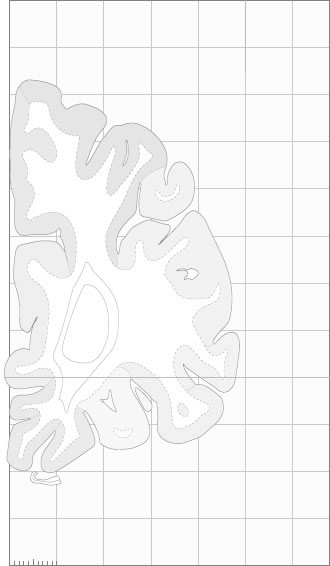

Frontal sections (Nissl) from the Atlas Brain:

Macroscopy

Schematic

Slice ID:

r1-0251

Plate NR:

04-05

Position:

-40,5 mm